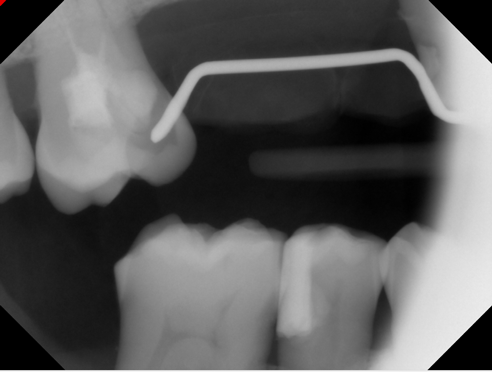

Fig 8. A 77-yearold

male patient presented with a distal lesion on tooth No. 2, previously treated with restorations that had failed.

Fig 8A

Fig 8B

A 77-year-old male patient presented in the author's AEGD Residency Program clinic with a chief complaint of sensitivity in the maxillary right posterior area. He had an unremarkable health history, and after a thorough examination, he was presented with several treatment options: minimally invasive drill access, performed laterally, filled with glass ionomer (poor prognosis); distal occlusal composite resin with an occlusal approach (preexisting occlusal resin apparent); or a distal occlusal ceramic onlay. The patient chose the first option of restoration with glass ionomer.

Figure 8A is a radiograph revealing deep root caries previously restored temporarily by a resident at the AEGD Residency Program clinic with glass ionomer utilizing a lateral rather than occlusal approach. After the glass ionomer failed to adhere, another resident again attempted a lateral approach that resulted in the restoration shown in Figure 8B. A third resident had success with an occlusal approach, removing a failed occlusal composite to access the distal  (Figure 9). This attempt was successful both in the preparation of the lesion and in the placement of a dual- cure bulk-fill flowable (Bulk EZ Plus, Zest Dental Solutions; alternatively: HyperFIL®, Parkell; Fill-Up!, Coltene) extruded through a bendable needle (Figure 10). Figure 11 shows the final preparation after tissue removal was accomplished with rotary gingitage; note that this was performed with the rubber dam in place. An air abrasion device (Groman Etchmaster, Groman Dental; alternatively: PrepStart H2O, Zest Dental Solutions; Bioclear Blaster, Bioclear) was used with potassium bicarbonate to remove biofilm prior to acid etching (Figure 12). Phosphoric acid 37% was utilized in a total etch fashion (Fig- ure 13 and Figure 14) for 20 seconds. Figure 15 shows the universal bond (Scotchbond Universal, 3M; alternatively: All-Bond Universal®, BISCO; Prelude One, Danville Materials) with metha- cryloyloxydecyl dihydrogen phosphate (MDP) being scrubbed into the cavity for 20 seconds. After air thinning for 20 seconds, the adhesive was light cured for 40 seconds at 1,200 mw/cm2power density (Figure 16).